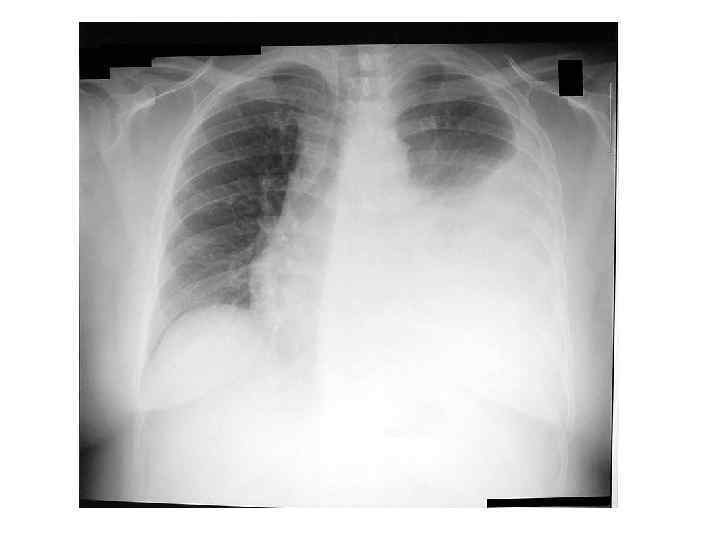

Характерно, что при изменении положения тела больного линия Дамуазо не смещается, так как над верхней границей экссудата происходит слипание между собой воспалённых листков плевры (при собой воспалённых листков плевры ( гидротораксе гомогенная тень жидкости с верхней границей смещается при наклоне тела). По мере накопления плеврального выпота линия Дамуазо постепенно укорачивается и может не определяться при тотальном заполнении плевральной полости. Рентгенологически линии Дамуазо соответствует граница затемнения, обусловленного жидкостью в плевральной полости